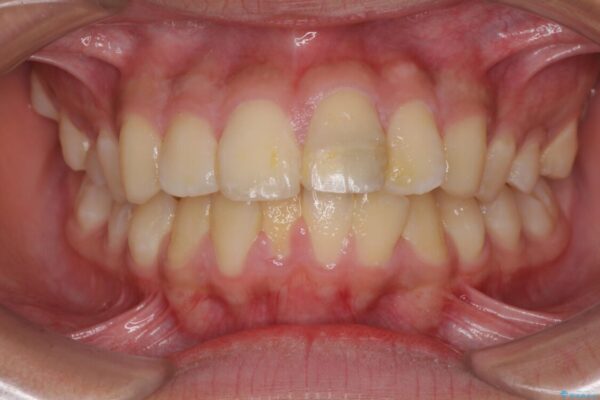

治療前

• 膨らんだ口元 ワイヤー装置での抜歯矯正 治療前画像

口元の突出感を気にして来院された患者様です。

上下前歯が著しく前突している状態であったので、上下左右の第1小臼歯4本を抜歯し、ワイヤー装置にて矯正治療を行うこととしました。